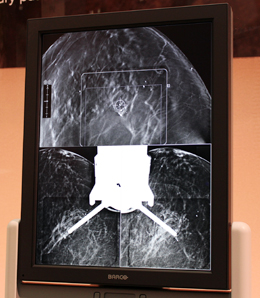

トモバイオプシーの位置決め画面

(上:トモシンセシス画像上でターゲットを指定,下:ステレオ画像)

従来のマンモグラフィを用いたバイオプシーでは,位置決めをするのにスカウト撮影のあと,角度を変えて2回撮影するステレオ撮影を行い,2枚の画像それぞれでターゲットの指定(クリック)を行う必要があった。

これに対してトモバイオプシーでは,トモシンセシス撮影を1回だけ行い,3D画像からターゲットの写り込んでいるスライスを探して,そのスライス上で1度ターゲットを指定するだけで,x,y,zの座標を指定することができる。これは,ターゲットの深さ方向が,スライス場所でわかるためである。トモシンセシス撮影後すぐに,穿刺に進むことができることで,乳房の圧迫時間,検査時間を短縮し,被検者と医師双方の負担を軽減することができる。あらかじめトモシンセシス撮影を行っていれば,ターゲットの位置を三次元的に把握して検査のシミュレーションを行うことも可能なため,生検時のポジショニングが容易になる。